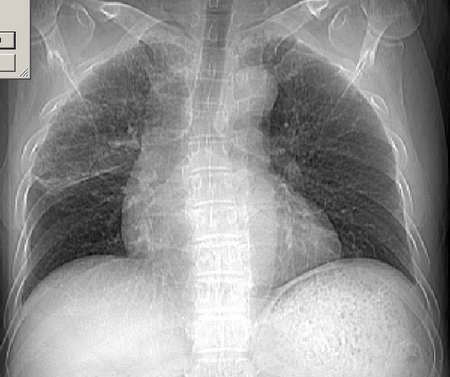

男54岁咳嗽咯痰2w,外院胸片示“右上大叶性肺炎抗炎治疗后部分吸收

可以考虑外院诊断:右上肺大叶性肺炎吸收期改变。

右肺上叶少量间质炎性表现,大叶性肺炎吸收期。